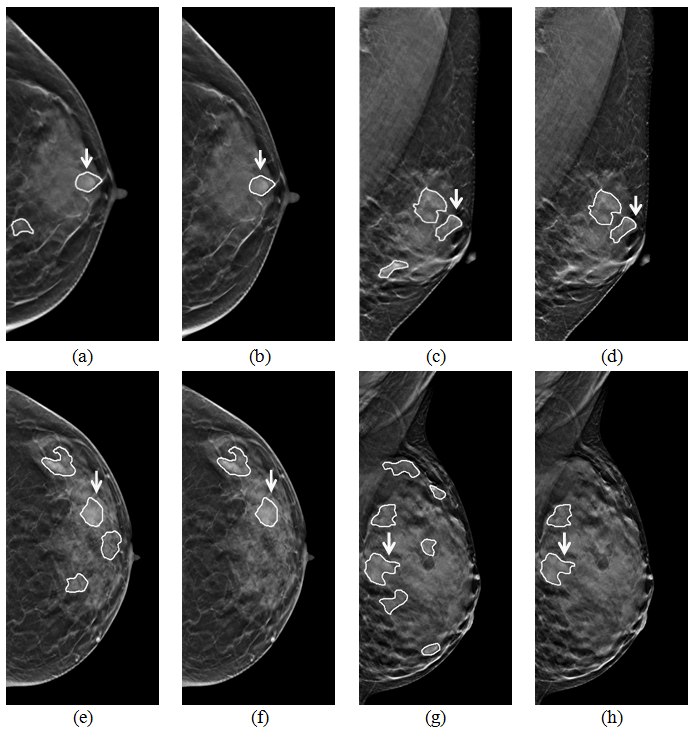

그림 4. 제안 방법의 false positive (FP) 감소 효과 예시. (a, c, e, g) 자동 병변 검출을 통해 생성된 병변 의심 영역이 그려진 단면영상 (실제 병변은 흰색 화살표로 표시함), (b, d, f, h) 제안 방법을 통해 FP가 감소된 단면영상.

- 최근 digital breast tomosynthesis (DBT)가 새로운 유방 영상 촬영술로 주목을 받고 있습니다. DBT의 2차원 투영영상(projection views)과 3차원 단면영상(reconstructed volume)은 상보적 영상 특성을 가지고 있어, 병변(mass) 자동 검출에 두 영상 정보를 모두 분석하는 것이 효과적 입니다. 이를 위해 본 논문은 두 영상에서 병변의 융합 특징 정보를 추출하고, boosting 및 다중 분류기 기반 병변 특징 선택/분류 방법을 제안하였습니다. 실험을 통해 두 영상 정보를 모두 분석 시 병변 분류 성능이 향상됨을 보였고 (그림 1), 분류에 중요한 병변 정보를 포함하여 자주 선택된 특징 정보들이 두 영상에 모두 분포하여 상보적임을 보였습니다 (그림 2). 또한 기존 정보 융합 방법 대비 우수한 분류 성능을 보여 (그림 3) DBT 투영영상과 단면영상 특징 융합 분석, 위양성 감소 (그림 4)에 효과적임을 보였습니다. 본 연구는 다중 영상 융합 분석, DBT 영상 특징 분석에 관심 있는 연구자들에게 도움이 될 좋은 정보라 생각합니다.